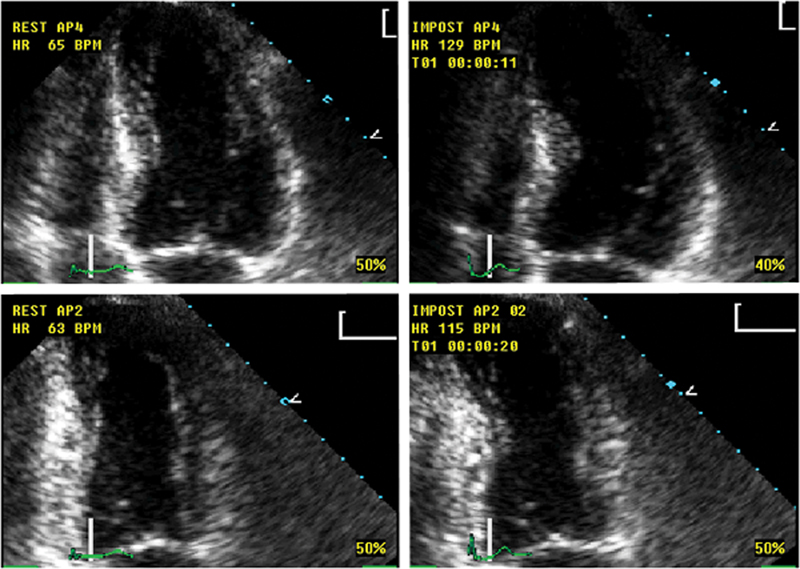

فحوصات تشخيصية لبعض امراض القلب والشرايين التاجية